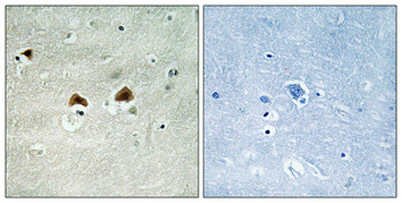

IF

IHC

Recomended Dilution Immunohistochemistry: 1/100 - 1/300. Immunofluorescence: 1/200 - 1/1000. ELISA: 1/5000. Not yet tested in other applications.